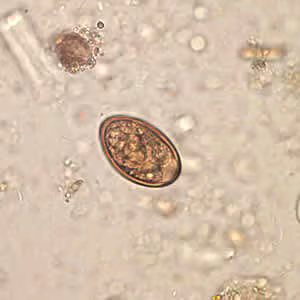

Dicrocoelium dendriticum adults.

Diagnosis is based on microscopic identification of eggs in the stool, duodenal, and/or bile fluid. Note that eggs may be detected in stool following consumption of liver infected with adult flukes; additional specimens should be collected to distinguish this spurious passage from a true infection. Adult flukes are rarely recovered.